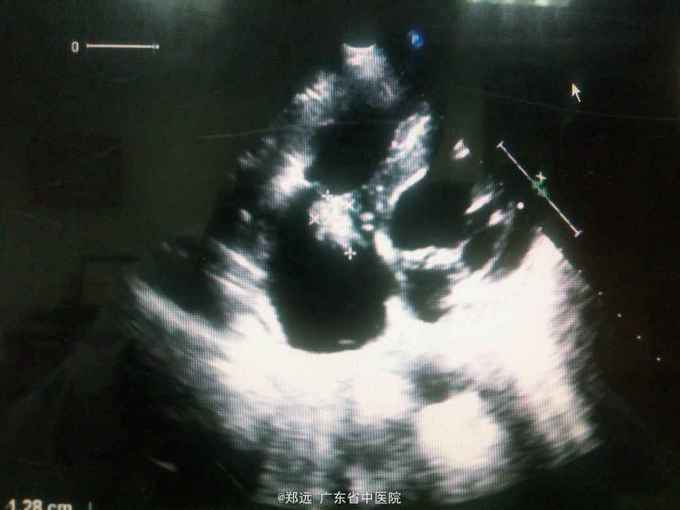

体查:双下肺湿啰音。三尖瓣区3/6级收缩期杂音。 胸部ct:双肺斑片结节影并空洞形成,左胸少量积液。血色素88克/升,白细胞11.48,中性粒81.3%,降钙素原14.84,ALT 121,AST 134.超声提示三尖瓣赘生物,三尖瓣大量返流。血培养金葡菌。

诊断:急性感染性心内膜炎,脓毒症,肺脓肿,丙型肝炎。 治疗:入院予万古霉素0.5克q6h,经治疗五日血象正常,降钙素原1.54,但仍反复高热,考虑肺脓肿合并阴性菌感染,加用头孢哌酮舒巴坦3克q12h,治疗五日仍有发热,血培养阴性,白细胞正常,降钙素原0.15,头孢哌酮舒巴坦改为美罗培南0.5克q8h,两日后无再发热,维持该方案至治疗四周后改予万古霉素0.5克q8h加美罗培南0.5克q12h继续治疗两周,复查超声提示三尖瓣熬生物较入院时缩小约三分之一,多次血培养阴性,胸部ct提示肺部炎症明显吸收予出院。出院后患者仍间发热,出院后约七周再次返院,查白细胞13.88,中性粒65.9%,血色素正常,降钙素原0.55,血培养提示溶血葡萄球菌,胸部ct示双肺多发感染灶,较前吸收,胸腔积液已吸收。予原万古霉素加美罗培南方案治疗,两日后无发热,治疗三周后多次血培养阴性,胸部ct提示肺部感染基本吸收,行三尖瓣赘生物切除并三尖瓣修补术,术中见三尖瓣后瓣瓣叶破坏严重,赘生物大小约2*1厘米。术后恢复良好,维持万古霉素加美罗培南治疗一周后改予万古霉素0.5克q8h加阿米卡星0.4克q12h治疗两周,赘生物及多次血培养阴性予出院。